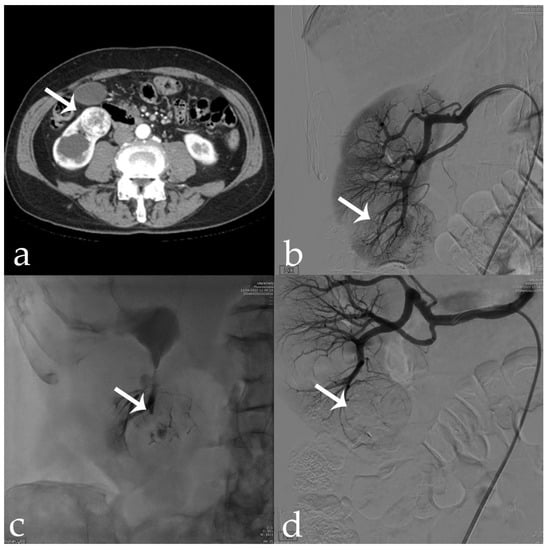

Figure 6. 56 yr old male with endo-exophytic RCC of the right kidney upper pole (30 × 20 mm): (a) pre-operative CECT; (b) pre-embolization DSA showing tumor vascular supply (arrow); (c) embolization procedure using stop-flow technique after super selective setting with a microcatheter-balloon inflated during 18-Onyx and indocyanine mixture administration; (d) post-procedural DSA showing complete tumor devascularization (arrow).